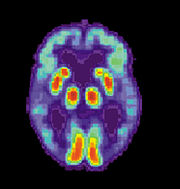

Dementia is by definition a clinical condition but not an exact diagnosis. Alzheimer's disease is usually diagnosed clinically from the patient history, collateral history from relatives, and clinical observations, based on the presence of characteristic neurological and neuropsychological features and the absence of alternative conditions. Advanced medical imaging with CT (Computed tomography) or MRI (Magnetic resonance imaging), and with SPECT (Single photon emission computed tomography) or PET (Positron emission tomography) are generally used to help to diagnose the subtype of dementia and exclude other cerebral pathology. Assessment of intellectual functioning including memory testing can further characterize the dementia. Medical organizations have created diagnostic criteria to ease and standardize the process for practicing physicians. Sometimes the diagnosis can be confirmed or made at postmortem when brain material is available and can be examined histologically.

Increasingly, the functional neuroimaging modalities of single photon emission computed tomography (SPECT) and positron emission tomography (PET) are being used to diagnose Alzheimer's, as they have shown similar ability to diagnose Alzheimer's disease as methods involving mental status examination. Furthermore, the ability of SPECT to differentiate Alzheimer's disease from other possible causes, in a patient already known to be suffering from dementia, appears to be superior to attempts to differentiate the cause of dementia cause by mental testing and history. A new technique known as "PiB PET" has been developed for directly and clearly imaging beta-amyloid deposits in vivo using a contrasting tracer that binds selectively to the Abeta deposits. Another recent objective marker of the disease is the analysis of cerebrospinal fluid for amyloid beta or tau proteins. Both advances (neuroimaging and cerebrospinal fluid analysis) have led to the proposal of new diagnostic criteria.